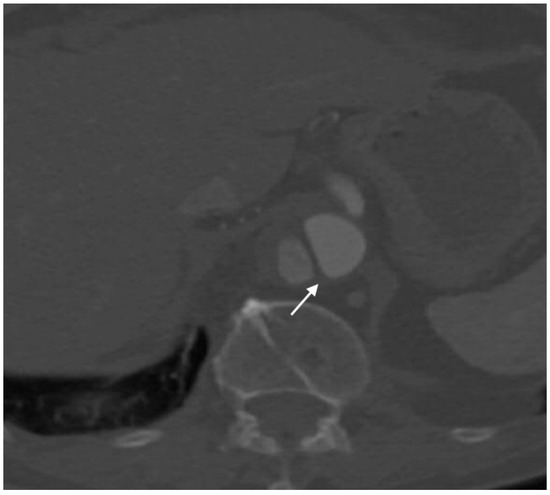

2.4.5. Pseudoaneurysm